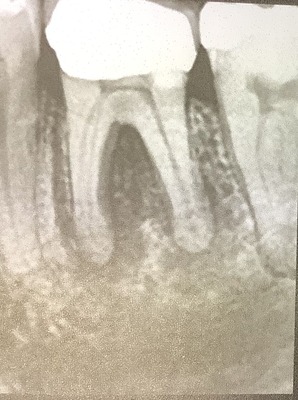

左下6番、根っ子と歯周病が一緒になっていてグレード2です。

シモンの分類だとおそらく神経の病気が最初で2次的に歯周病が起きている。

根っ子に影、骨もやせている

根っ子に影、骨もやせて、それぞれが別個にある